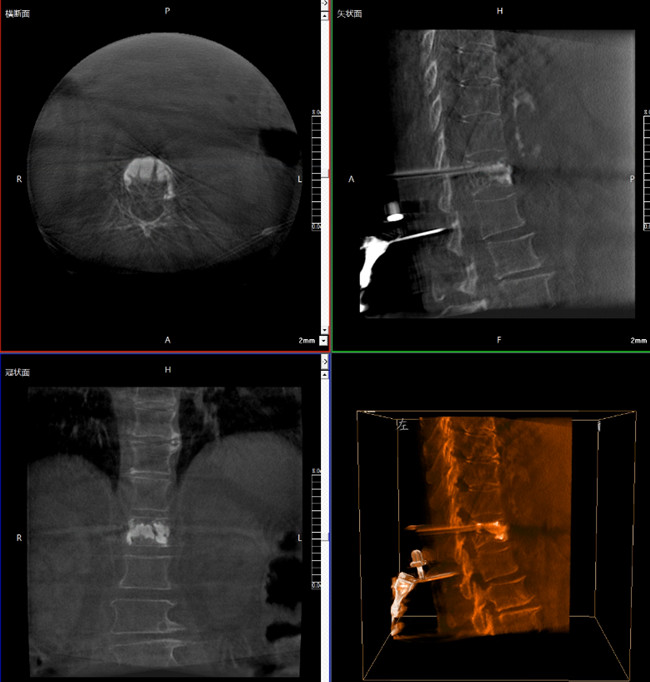

? 手術效果確認

*骨水泥置入效果良好

良好的臨床使用體驗源于普愛醫療骨科機器人導航系統和醫生的完美配合。亞毫米級的準確定位、直觀的術前規劃和機械臂的執行,使醫生無需擴大創口進行傷椎入針路徑定位,僅需術前三維重建即可全方位了解傷椎位置及穿刺路徑,除了極大的提高了一次性穿刺成功率,也大幅降低了手術對醫生經驗的要求,手術上手難度更低。